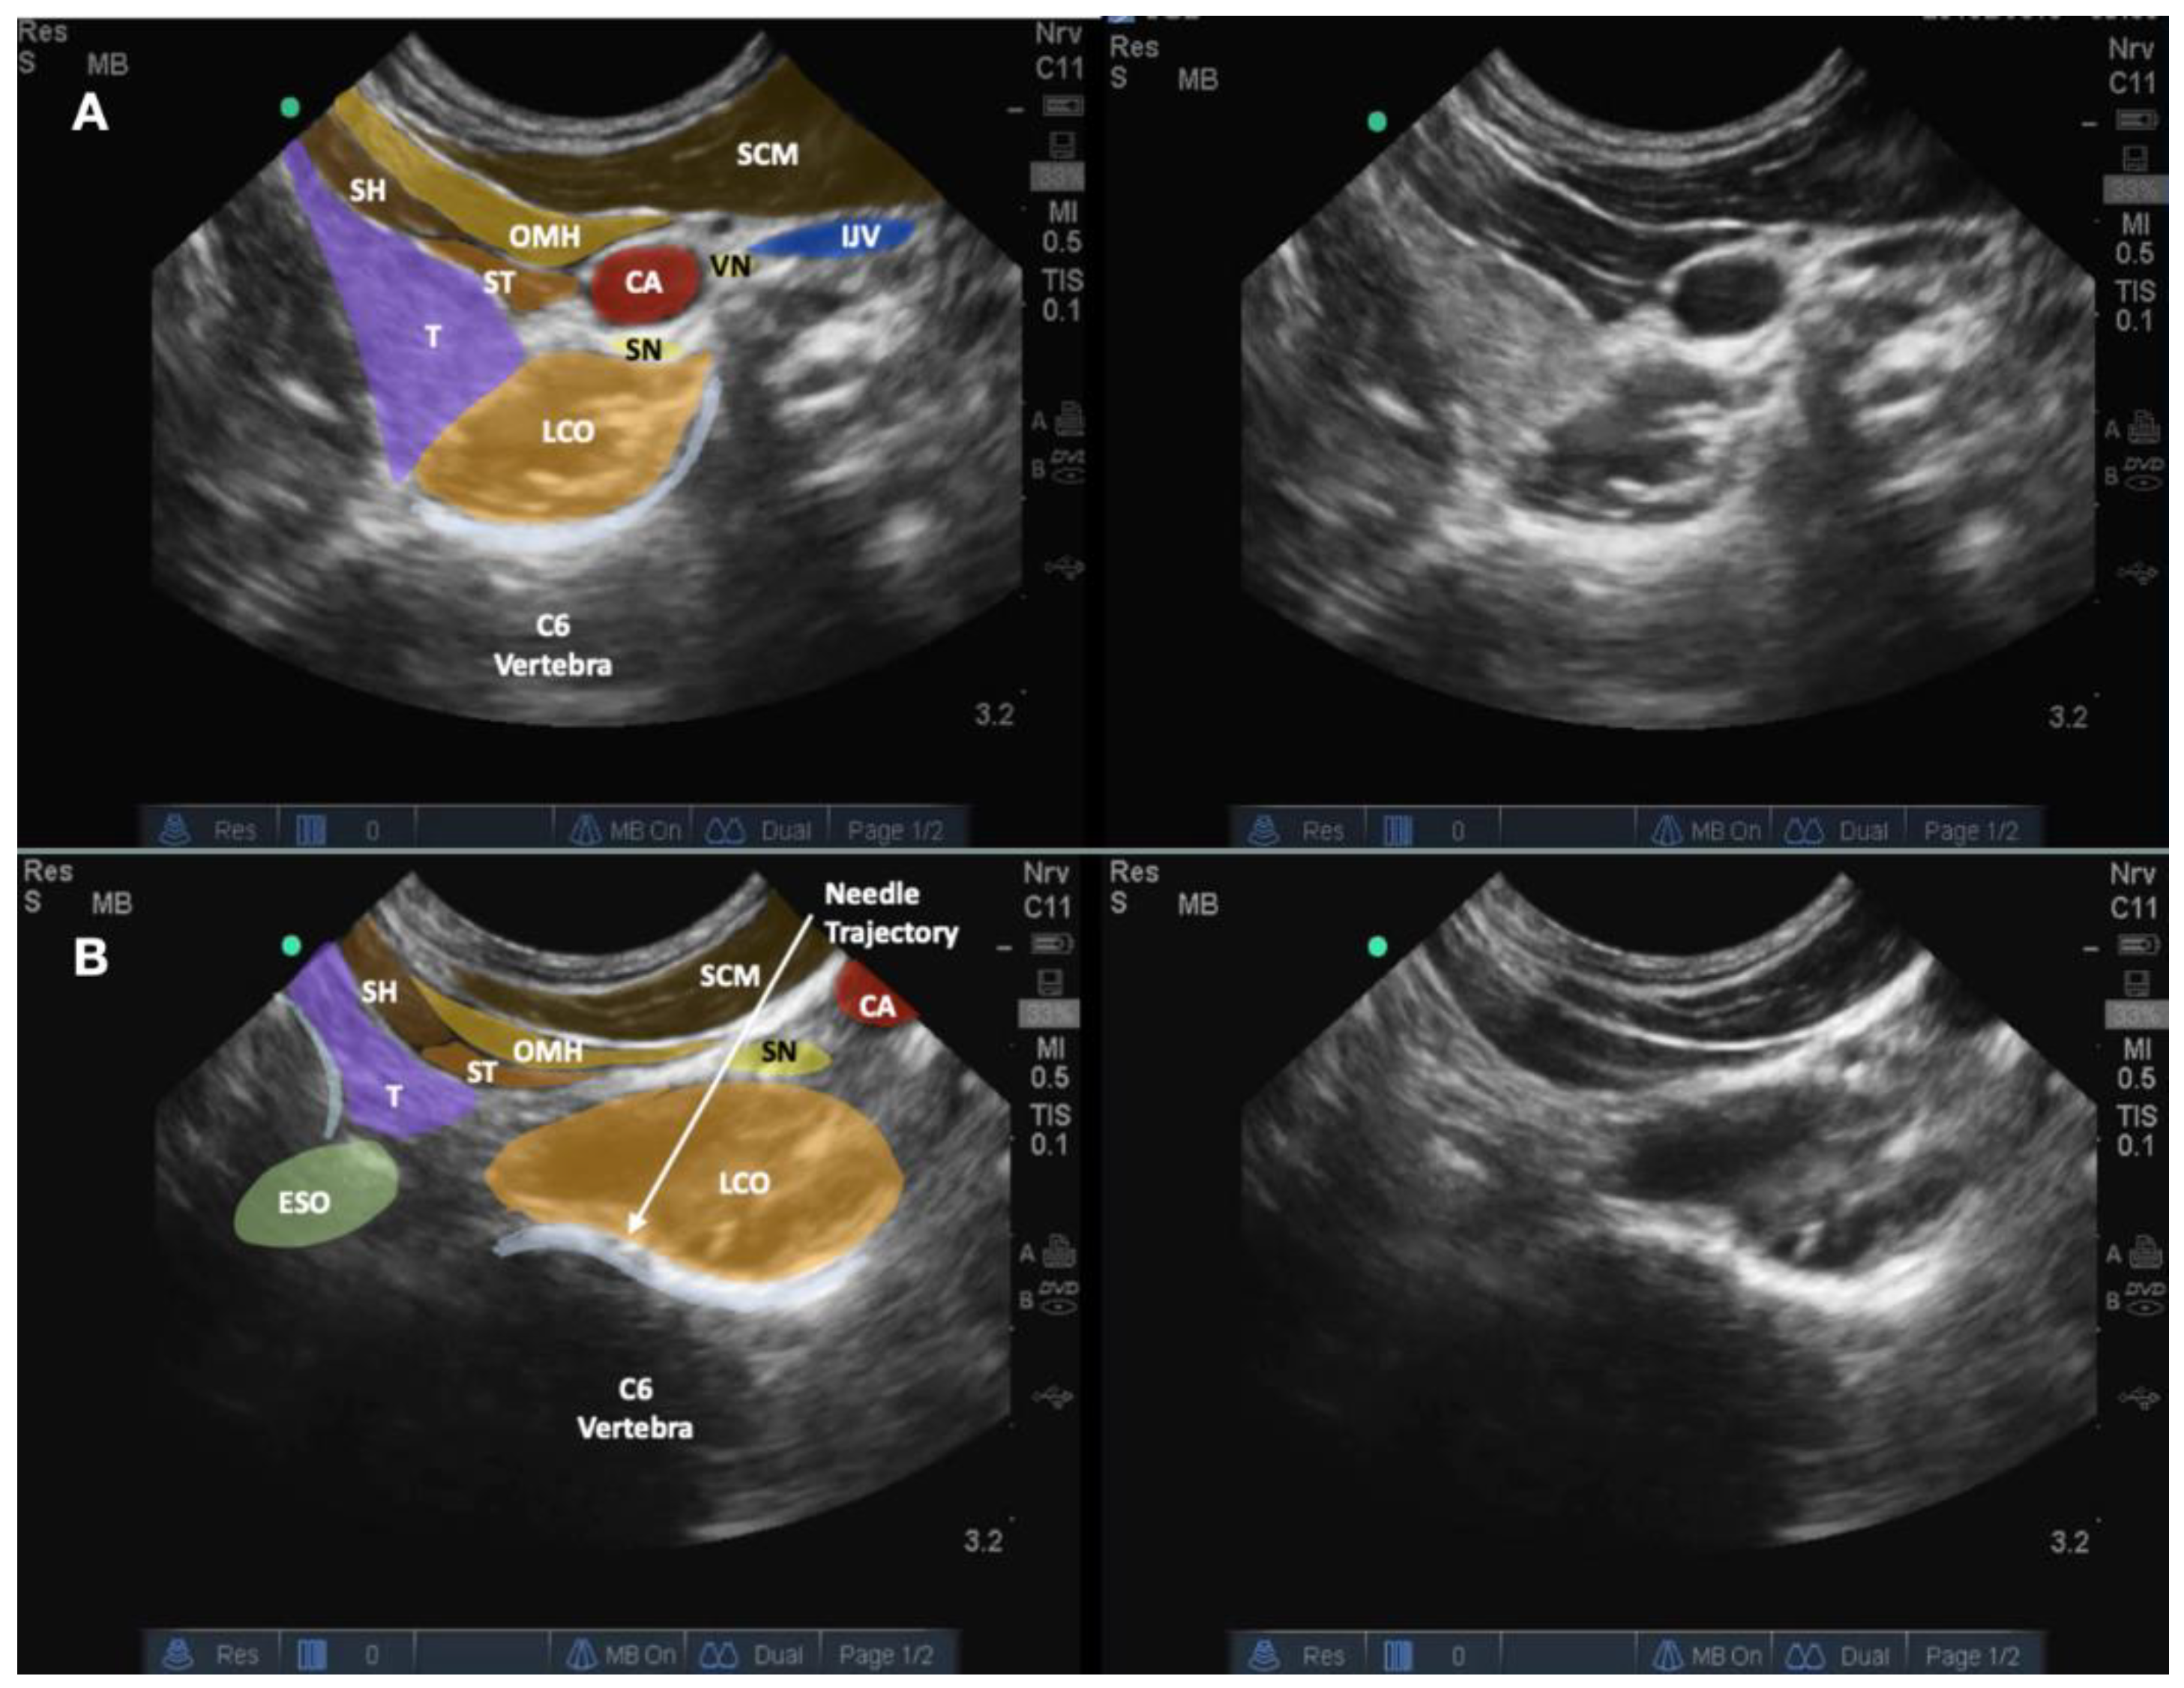

3. Technical Note